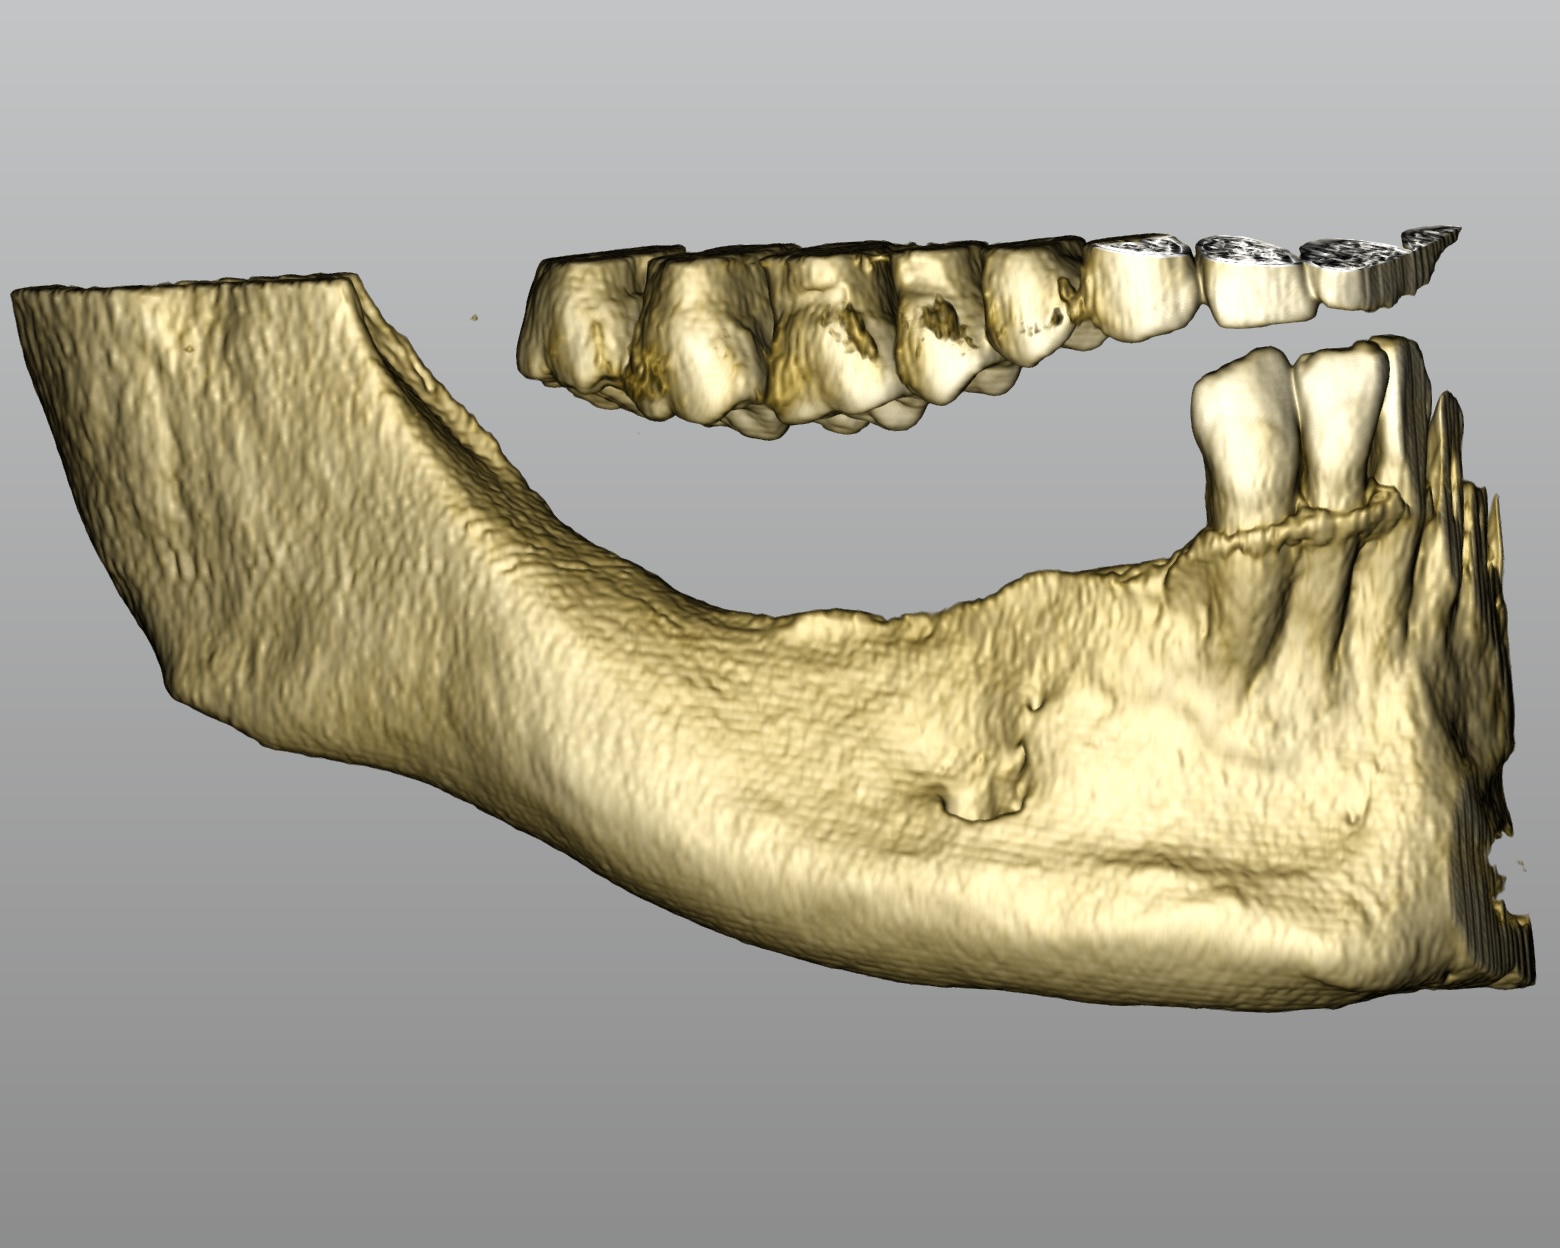

Una paziente di 56 anni, in buono stato di salute generale, si presenta all’attenzione del reparto di estetica dentale dell’Istituto Stomatologico Italiano con la richiesta di riabilitare, tramite soluzione implantare, la sua condizione di edentulia parziale. All’esame obiettivo intraorale è possibile apprezzare un’edentulia di classe II riferita al VI sestante, caratterizzata da un’importante atrofia ossea (Figure 1a-b).

La visualizzazione della CBCT (Figure 2a-b) permette di valutare tridimensionalmente l’atrofia riscontrata durante l’esame clinico. Le immagini ricavate dalla rx evidenziano come l’atrofia sia stata sottostimata rispetto alle aspettative, in quanto la sezione di mandibola mostra un aspetto a lama di coltello con un importante sottosquadro linguale. Prima di poter procedere al posizionamento implantare risulta quindi necessario intervenire con la rigenerazione del volume osseo corretto. Viene pertanto proposta alla paziente una chirurgia rigenerativa realizzata mediante l’ausilio di una griglia customizzata in titanio, realizzata sulla base della ricostruzione tridimensionale ricavata dalla Cone Beam.